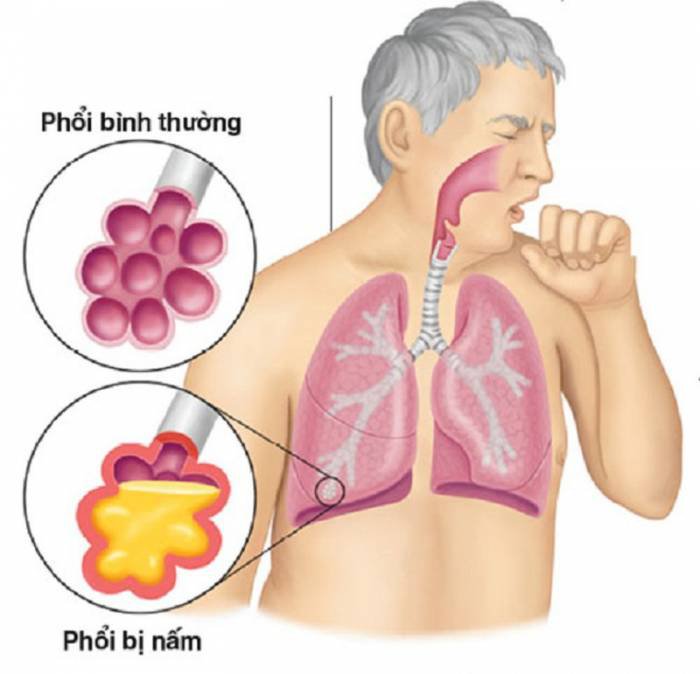

Là tình trạng nhiễm trùng đường phổi. Bệnh viêm phổi là tình trạng các phế nang trong phổi bị viêm do một nguyên nhân bất kỳ gây ra. Viêm phổi có thể xuất hiện tại một vị trí cố định hay một vài vùng. Nguy hiểm hơn là xuất hiện viêm toàn bộ phổi.

Viêm phổi do nấm

Người mắc bệnh viêm phổi do nấm thường là làm việc ở những nghề nghiệp có tính chất đặc thù như làm vườn, nông dân, lao công, công nhân xây dựng….Môi trường làm việc khiến họ vô tình bị hít phải bào tử của nấm, khiến chức năng phổi bị viêm.

Các tác động về môi trường và lối sống thiếu lành mạnh như tiêu thụ quá nhiều rượu bia và thuốc lá cũng khiến phổi bị yếu, tạo điều kiện cho nấm phát triển mạnh mẽ.